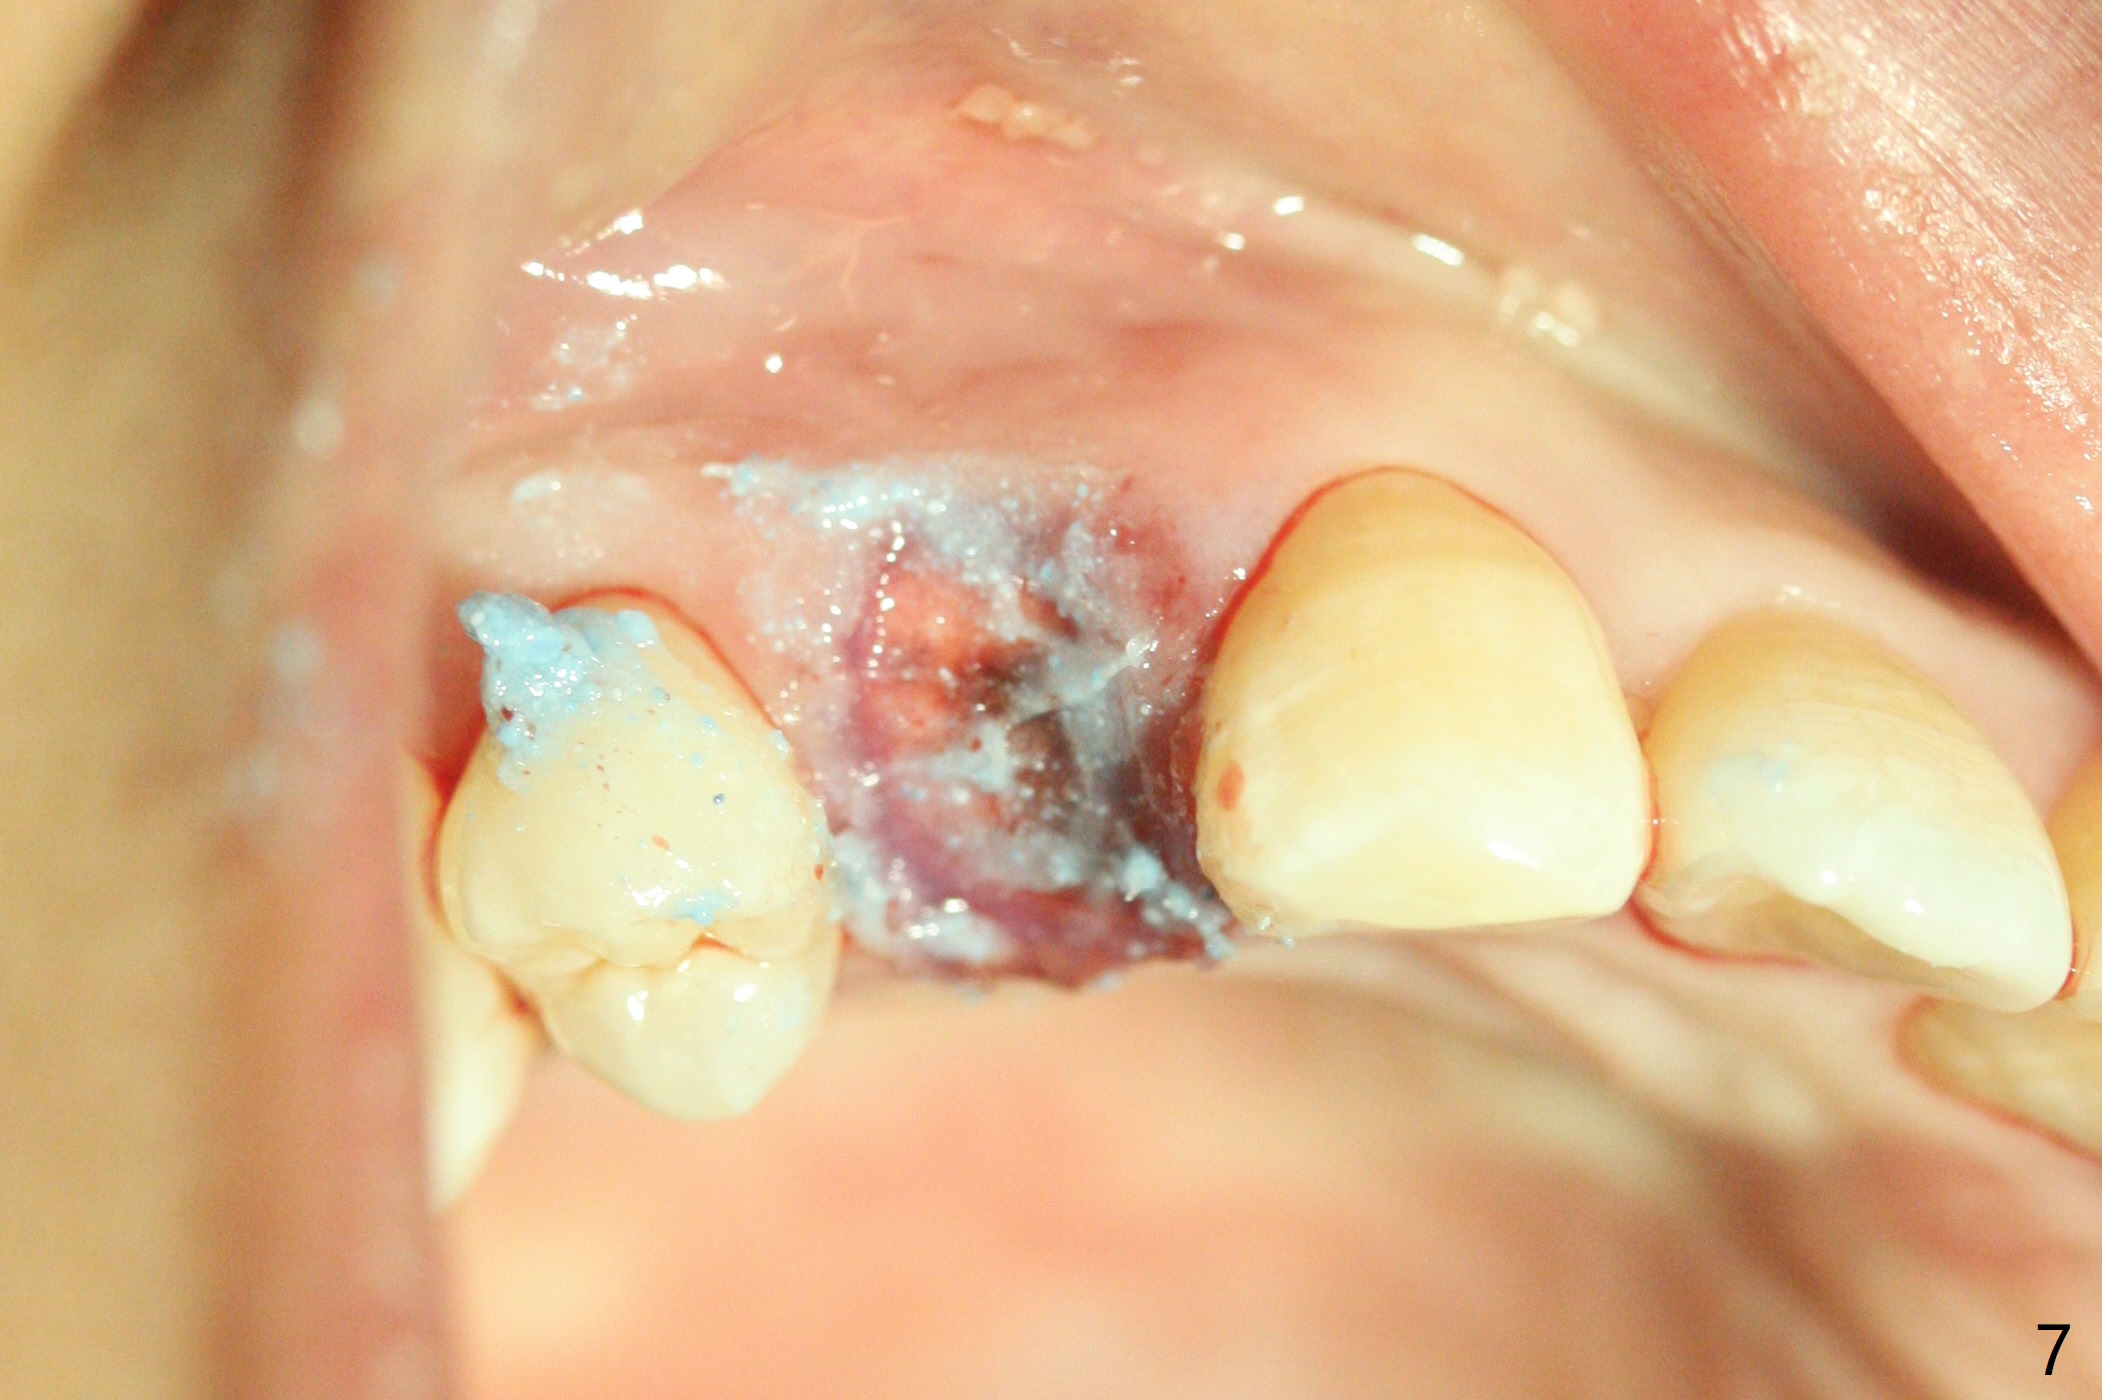

今天临床实践让我对植骨概念和操作有两方面突破,与大家分享讨论。PRF/sticky bone(粘性骨粉)以及血小板因子(成品)对软硬组织缺损修复重建无疑起到不可缺少作用。但是大多数拔牙病例并不是那么严重,放置骨粉和覆盖胶原膜足够了。为了避免费时的缝线固定胶原膜,介绍一种简易固定方法,助手可以做。31岁女不想保留严重龋坏右上4(图一至四,拍摄临床照片,与后期比较,但愿简易植骨不产生骨板塌陷),虽然术前根尖片显示根尖阴影(图四),术中没有根尖骨板缺失。估计没有严重骨板缺损,她又年轻,再生能力强,所以做简易植骨(异体骨,图五),也就是不需要PRF或者血小板因子,骨粉表面放置GEM CAP(9-12月吸收膜),由胶水固定(图六),在放置牙周敷料前,在胶原膜表面涂一层含有抗单纯疱疹病毒凡士林(图七),但愿敷料脱落时,不至于把胶原膜带下来。术后第六天,病人由于左上第二磨牙不适回来,说敷料脱落,没有不适,要求检查,其实膜也丢失(图八,九),骨粉好像挺稳定,没有做如何处理,尽管少量骨粉离开牙槽窝(<)。